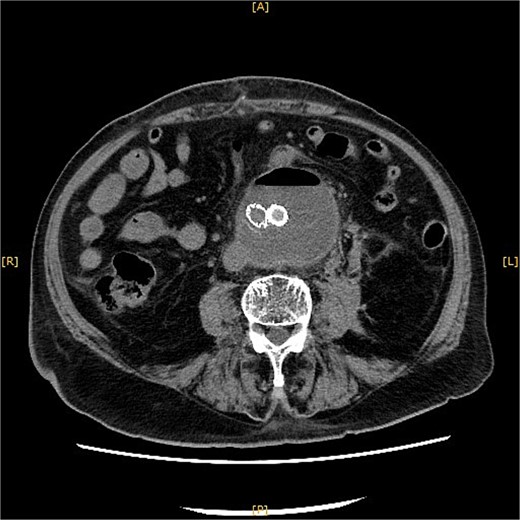

A plain CT on POD 14 showed a reduction in the aneurysm size with no apparent leaks.